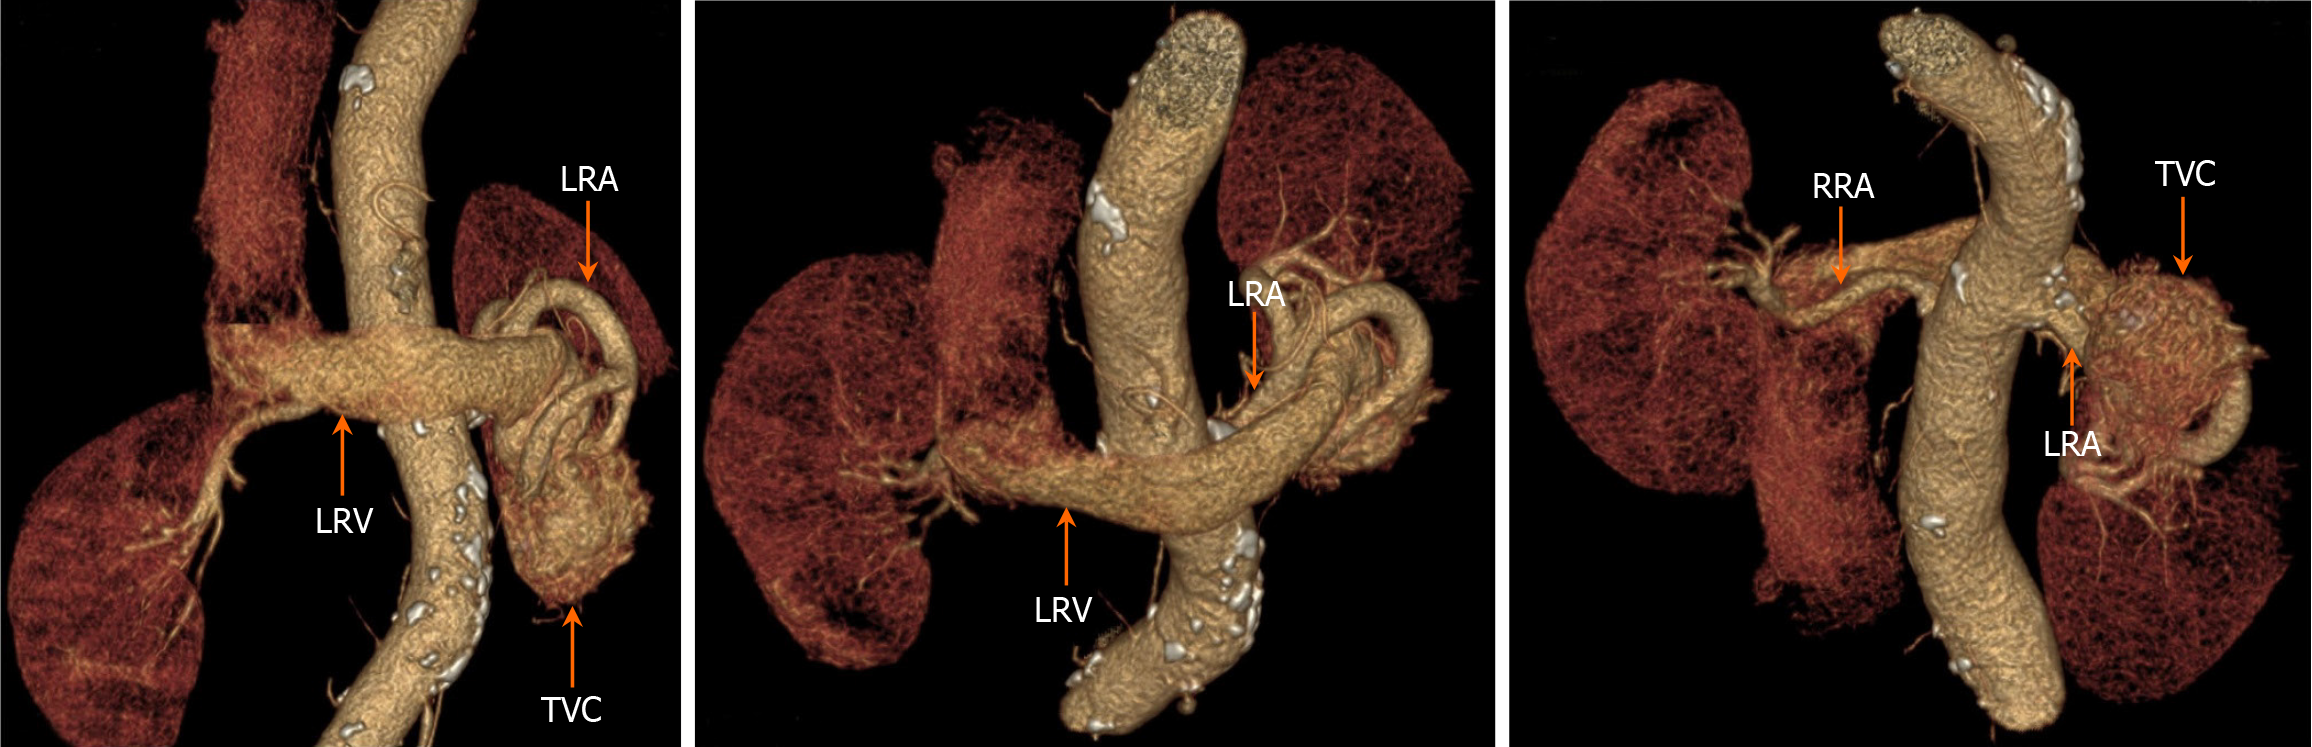

The results of enhanced CT showed the left renal artery was the feeding artery and the left renal vein was the draining vein, thus inferring several obvious fistula positions. In addition, renal neoplastic lesions were excluded, but the smaller fistula could not be clearly identified. 3D-CTA focuses on blood vessels, which can form clear, multi-plane and multi-angle 3D reconstructed images to provide more comprehensive morphological information of blood vessels. This helps doctors comprehensively understand the condition and provides accurate information for interventional treatment. On June 28, 2023, a 3D-CTA examination of the renal arteries revealed thickening of the left renal artery, localized communication with the left renal vein, aneurysmal dilatation of the left renal vein, and irregularly massed vascular shadows with vasculature-like enhancement in the lower pole of the left kidney (Figure 5). The results of 3D-CTA examination suggested that the left renal vascular tortuosity and tumor-like extension of the adjacent left renal vein might be considered as a diagnosis of RAVF.